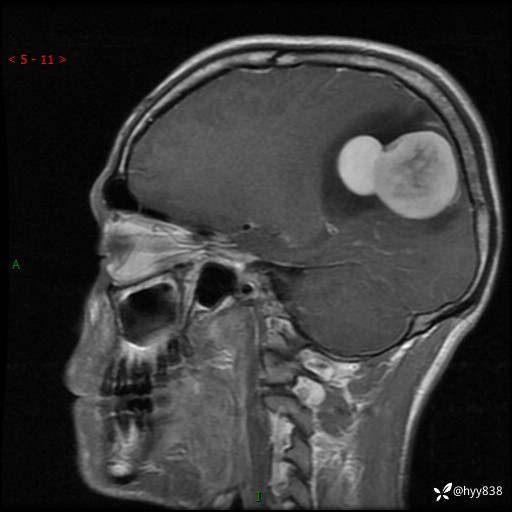

病例年轻小伙,头痛伴呕吐半年,渐进性加重1月。疑难病例,第一次见--结果公布~

性别:男

年龄:21岁

简要病史:头痛伴呕吐半年,渐进性加重1月

颅脑MRI平扫+增强